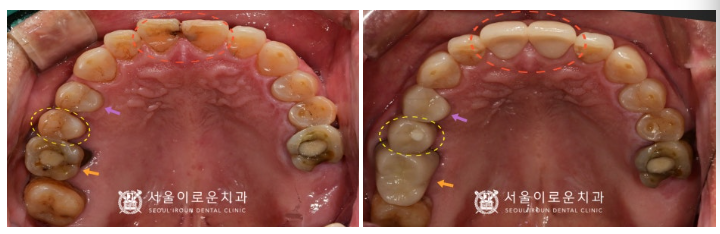

다행히 충치가 신경까지

진행이 되지 않은 상태라

신경치료는 하지 않아도 되는 상황이었지만

충치가 있는 치아머리 일부를 삭제하고 나면

잔존 치질량이 얼마 되지 않아

치아가 약해지기 때문에

충치 제거 후 레진으로 보강한 뒤

크라운 치료를 계획하였습니다.

오른쪽 위턱 두 번째 작은 어금니(#15)는

발치 후 염증조직을 깨끗하게 제거하고

소독한 후에 뼈이식을 동반한

임플란트 즉시 식립을 도와드렸는데요.

또한 오른쪽 위턱 첫 번째 큰 어금니(#16)와

앞니(#11,12) 모두

충치를 말끔하게 제거한 뒤

레진으로 보강하여

크라운 치료를 도와드렸습니다.